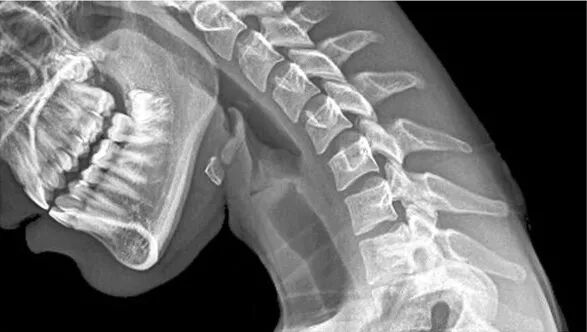

颈部是人体神经最密集的部位,所以一旦车辆发生碰撞,颈部受到的冲击就是较为严重的。

即使在只有 10 公里/小时的时速下发生碰撞,车辆的加速与减速的力量全部挤压在脆弱的颈部,就很容易发生受伤的事故。

医学家把颈部受伤分成三种程度:

1. 最轻微的,颈部僵硬或稍许疼痛;

2. 较为严重,包括肌肉与骨骼损伤,颈部动作范围到达极限。

3. 最严重,会导致神经系统出现问题甚至瘫痪。